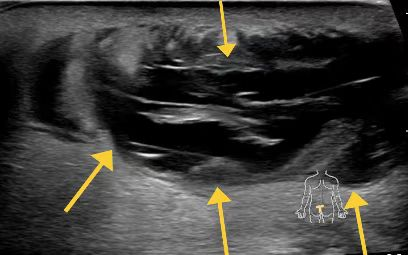

Bourak Chousein 等人一項(xiàng)RCT研究了PRP對(duì)手術(shù)藏毛竇的影響,納入 140 例診斷為藏毛竇疾病的患者?;颊弑浑S機(jī)分為 2 組;一組患者術(shù)后使用標(biāo)準(zhǔn)敷料進(jìn)行隨訪,另一組患者在標(biāo)準(zhǔn)敷料的基礎(chǔ)上接受 PRP 治療。在本研究中,將 2 組之間的傷口愈合率確定為主要目標(biāo)。

結(jié)果術(shù)后第 10 天檢測(cè)到傷口愈合率存在差異 (P = 0.007)。對(duì)照組患者的平均傷口愈合時(shí)間為 41.1 ± 11.0 天,而 PRP 組為 23.6 ± 8.5 天(P < 0.001)。確定 PRP 組患者的傷口閉合時(shí)間更快。

應(yīng)用 PRP 的患者,術(shù)后以 0.5 mL PRP 注射到許多部位。

術(shù)后第 2 天 (A)、4 (B)、6 (C)、10 (D)、15 (E) 和 20 (F)。

前瞻性隨機(jī)研究中,我們發(fā)現(xiàn) PRP 顯著著提高了傷口愈合率和患者舒適度,復(fù)發(fā)率低于 1%,疼痛最小。